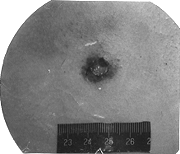

指彈頭射入人體時,在接觸處洞穿皮膚所形成的創口。射擊距離是以射入口是否擁有射擊附加成分來區別的。接觸射擊:指一槍口接觸皮膚進行的射擊。近距離射擊:指手槍在50cm以內,步槍在100cm以內進行的射擊。遠距離設計:指手槍在50cm以外,步槍在100cm以外進行的射擊。形態特徵:以近距離射擊的射入口為例:擦拭圈、衝撞輪(挫傷輪)、火藥顆粒(射擊附加成分)、煙火痕跡(射擊附加成分)。遠距離射擊的射入口沒有射擊附加成分。接觸射擊的射入口呈星芒狀,有礦坑現象。射創管

這兩個問題與案件性質有密切聯繫。自殺一般都是近距離或接觸射擊,而且射擊方向多為由前向後或側方射擊;遠距離射擊或自後方射擊則一般見於他殺或意外。要分清射擊距離的遠近和射擊方向,最重要的是要識別射入口和射出口,以及近距離射擊時射入口應具有的一些特徵。射入口一般呈圓形或卵圓形,當槍口緊密接觸人體射擊時,射入口則呈星芒狀裂開。射入口常有組織缺損,而使射入口處的皮膚不能完全合攏。射入口內緣皮膚上有彈頭穿過時與皮膚摩擦碰撞形成的一圈擦傷和挫傷,習慣上稱為衝撞輪或挫傷輪,寬約l一2mm,始為鮮紅色,後因水分揮發而皮革樣化,變成棕黃色。同時,彈頭表面粘附的油污、鐵鏽、菸灰、金屬粉末和火藥煙渣等也被留在射入口內緣皮膚上,習慣上稱為擦拭輪或污垢輪,寬約lmm,呈灰黑色,與上述挫傷輪常重疊一起不能分開。擦拭輪在裸露部位的皮膚上較明顯,如彈頭進入人體前穿過較厚的衣服,則擦拭輪可不明顯,但挫傷輪則肯定有。在近距離射擊時,射入口周圍常有火藥作用的痕跡,它們包括:灰色的火藥煙暈、未燃燒盡的火藥顆粒沉著在射入口周圍的皮膚上。有時因火藥燃燒不完全產生的一氧化碳,與射入口血液內的血紅蛋白和肌肉中的肌紅蛋白結合成碳氧血紅蛋白,而使射入口周圍出現環狀的鮮紅色澤。射入口周圍的皮膚和毛髮,有時還能檢見燒傷的痕跡。 射出口常呈裂隙狀或星芒狀,一般無組織缺損,因此創口周圍的皮膚可完全合攏。周圍皮膚上也無上述火藥作用的痕跡,即無挫傷輪、擦拭輪、火藥煙暈、火藥顆粒沉著和皮膚環狀發紅的徵象。藉此可以與射入口區別開來。近距離射擊指火藥作用範圍內的射擊,槍口與人體間的距離依槍枝種類而有差別。一般小型手槍為20一30cm;手槍為40一50cm;步槍約100cm;滑筒槍約50cm。近距離射擊時,在射入口周圍能檢出上述火藥作用的痕跡。法醫學上將槍口接觸人體的射擊稱作接觸射擊,依接觸情況不同又分緊密接觸、非緊密接觸和部分接觸射擊,此時射入口多呈星芒狀,組織缺損嚴重,火藥作用明顯。如為緊密接觸射擊,還能在射入口周圍皮膚上檢見槍口壓迫形成的“槍口印痕”。